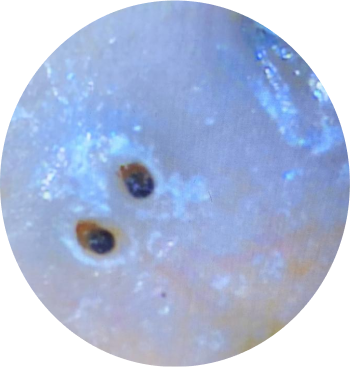

Gary’s scalp condition was caused by head lice, which developed due to consistently undried hair and poor scalp hygiene. This neglect led to severe irritation, infection, and patchy hair loss, with noticeable clumps of hair falling out.

• Lice Removal and Scalp Cleansing: A thorough cleansing process was carried out to remove lice and their eggs, ensuring the scalp was disinfected and free from infestations.